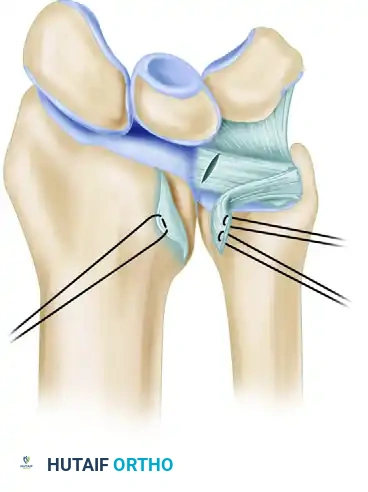

5. Transosseous Drill Holes and Suture Passage

- Utilize a 1.2-mm Kirschner wire (or a drill bit of equivalent size) to create a line of four side-by-side drill holes through the distal radius.

- The trajectory of these holes must be precise: drill from the dorsal surface of the distal radius (dorsoradial) directing the wire palmar-ulnar, ensuring the drill point exits exactly at the distal margin of the sigmoid notch, at the ulnar (medial) border of the lunate fossa.

- Select a high-tensile, absorbable suture—typically 2-0 or 3-0 polyglactin 910 (Vicryl) or polydioxanone (PDS)—armed with a small, round needle.

- Place horizontal mattress sutures into the substance of the avulsed TFCC. Pass the suture from the proximal undersurface to the distal surface of the fibrocartilage to ensure a secure bite.

Figure B: Suture placement into the TFCC through holes drilled in the dorsoulnar aspect of the distal radius. Horizontal mattress sutures are directed in a palmar and ulnar direction to exit at the edge of the lunate fossa and sigmoid notch.

- Remove the small needles from the sutures.

- To retrieve the sutures through the transosseous tunnels, pass a straight needle (without suture) in reverse through the drill holes to capture and pull the ends of the suture pairs dorsally. Alternatively, a wire loop (Hewson suture passer) or a specialized nitinol suture passer can be utilized with excellent efficacy.